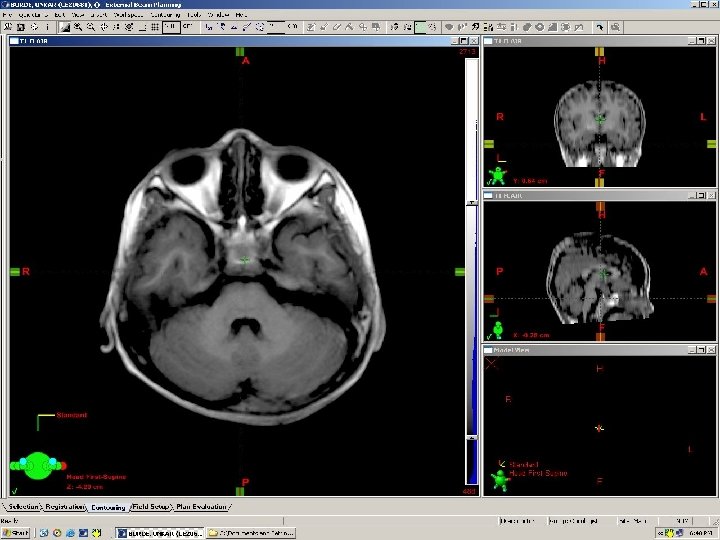

lens Eye ball Optic nerve Ethmoid air cells Temporal horn of lat ventricle Nasopharynx Internal carotid artery Inf. Temporal gyrus Inf pons Vermis Formation of Basilar artery Parieto occipital sulcus Transverse Sinus